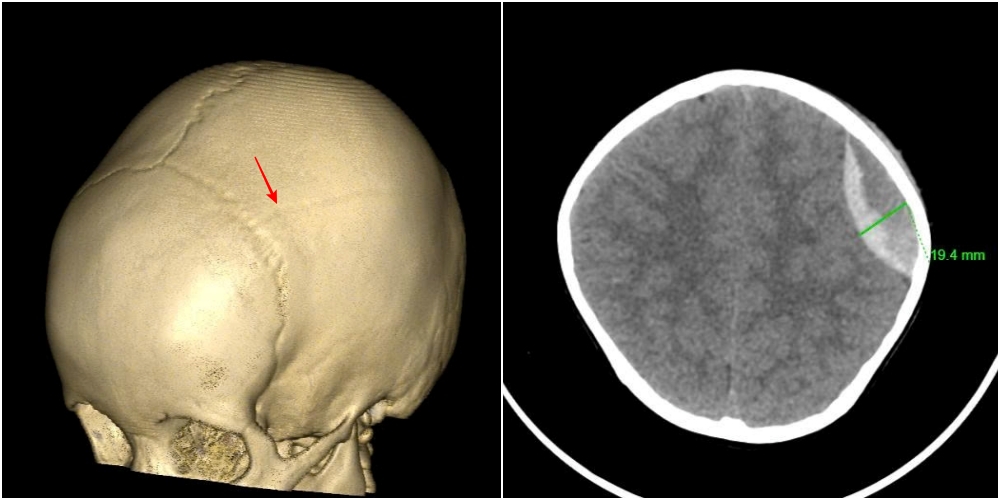

Hình ảnh vỡ xương sọ, tụ máu ngoài màng cứng đỉnh trái của bệnh nhi 3 tuổi

Kết quả chụp cắt lớp vi tính cho thấy hình ảnh vỡ xương sọ, chảy máu ngoài màng cứng đỉnh trái. Các bác sĩ chẩn đoán bệnh nhi bị chấn thương sọ não do ngã, vỡ xương, tụ máu ngoài màng cứng đỉnh trái. Ngay lập tức, các bác sĩ chuyên ngành ngoại thần kinh phối hợp cùng khoa Gây mê hồi sức tiến hành phẫu thuật cấp cứu lấy máu tụ, cầm máu kỹ, đặt và cố định lại xương sọ. Ca mổ diễn ra thuận lợi trong khoảng 30 phút. Sau phẫu thuật, bệnh nhi tỉnh nhanh, bú tốt và chơi ngoan chỉ sau 2 ngày điều trị, sức khỏe dần ổn định.